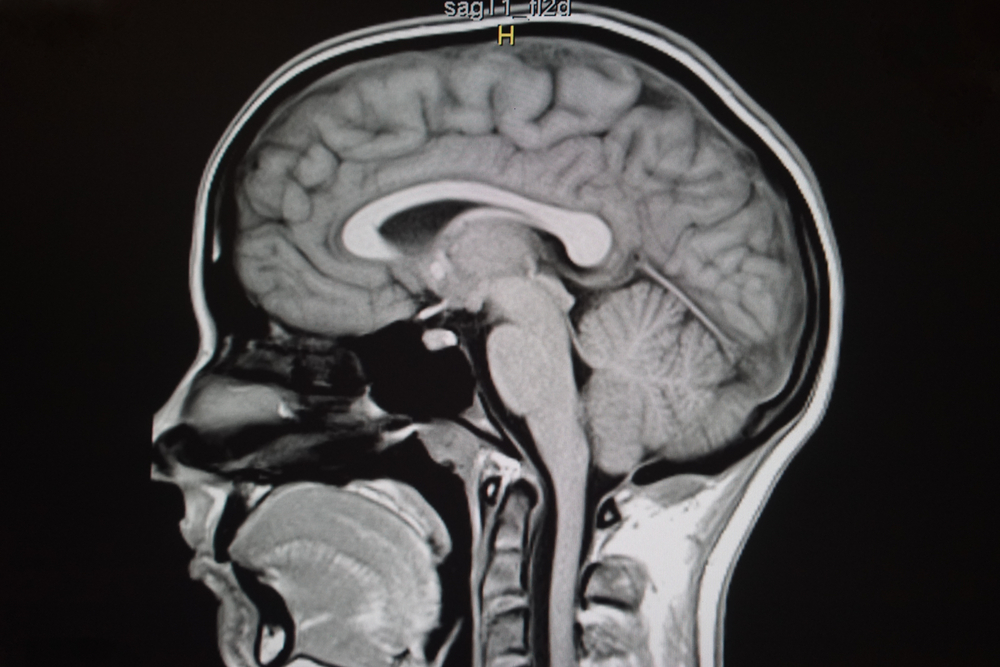

Синдром пустого турецкого седла — это совокупность клинических и анатомических признаков, связанных с проникновением мягкой мозговой оболочки из субарахноидального пространства в костное образование черепа...